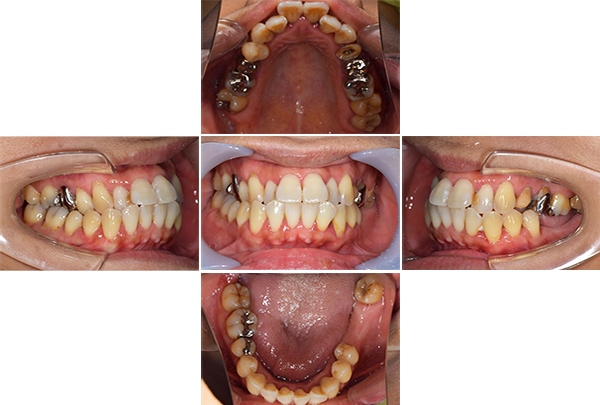

| 年齢 | 30代女性 |

|---|---|

| 主訴 | 左上の奥歯が何もしなくても痛い。悪いところは全部治したい。 |

| 治療期間 | 1年半 |

| 費用 | ・右上567FCZインプラント: 440,000円×3 ・右上567サイナスリフト+サージカルガイド+IV: 220,000円+55,000円+77,000円 |

※全て税込となります。

上顎左側第一・第二大臼歯は歯周病と根尖性歯周炎により保存不可能。また上顎左側第二小臼歯は縁下カリエス(根の虫歯)と短根のため部分矯正もできず予後不良と診断、抜歯をする経緯となりました。前歯部にはクラウンでの補綴修復が見られ下顎右側臼歯部には大きなカリエス様透過像が見られました。

【担当医師所見】

コーンビームCT像を確認すると左側上顎の骨は無くインプラント埋入の際は上顎骨に骨造成が必要と思われたため上顎洞挙上術(サイナスリフト)を併用、インプラント埋入を行うプランとしました。

また欠損部位の大きさを考えるとサージカルガイドの使用が必要と思われたため今回使用した。さらにオペの強度を考え静脈内鎮静法下にてオペを行った。

処置前では黒い透過像(骨が無い)があるが骨造成後1年経過、インプラントテック(仮歯)を入れた際では上顎洞内及びインプラント周囲に白い不透過像(骨がある)が確認できます。

治療前、左上大臼歯部は咬合面(咬む面)も無くカリエス(虫歯)も大きいものでした。

治療後、理想的な位置にインプラントが埋入され正しく咬むことができるようになりました。

| 治療方針 | ・歯周病基本治療を行う ・かみ合わせのズレを修正する ・抜歯後にインプラント治療を行う |

| 治療内容 | ・歯周基本治療終了後に左上の抜歯を行う ・抜歯部位の治癒後インプラント埋入のための骨造成を行い骨の完成を待つ ・骨の完成後にインプラント埋入しインプラントと骨の結合した後に上部構造(かぶせ物)を入れる |

| 特記事項 | 特になし |